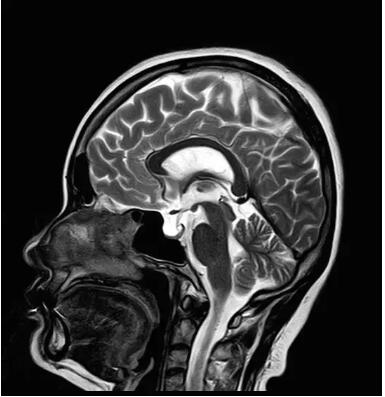

圖:搭載Pure射頻鏈全新一代1.5T磁共振

佳能磁共振推出了全新一代Vantage Elan1.5T磁共振,這款日本原裝進口的 1.5T磁共振,集當今磁共振創(chuàng)新科技成果于一身: